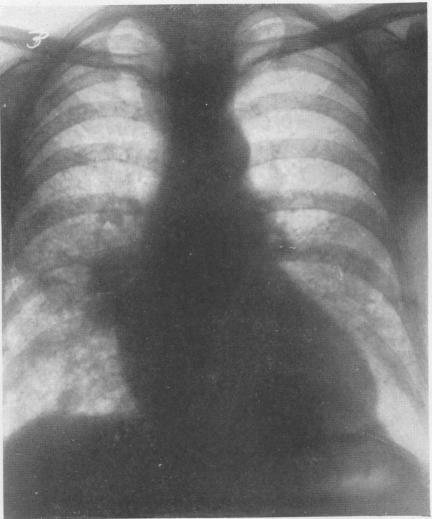

McLAUGHLIN A I G, ROGERS E, DUNHAM K C

Br J Ind Med. 1949 Jul;6(3):184-94. doi: 10.1136/oem.6.3.184.